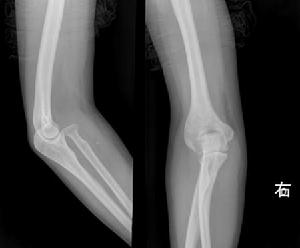

6.X線攝片顯示肘關節有骨質破壞,關節間隙狹窄或消失。

X線攝片單純滑膜結核顯示局部骨質疏鬆和軟組織腫脹。在鷹嘴或外踝中心型結核,可見死骨形成。若病變累及鄰近骨幹,可見骨膜性新骨形成。早期全關節結核,可見關節邊緣局限性骨質破壞,或輕度關節軟骨下骨板模糊。晚期全關節結核,關節軟骨下骨板廣泛模糊,關節間隙變窄。竇道繼發感染骨質顯示硬化。

治療後,全身情況良好,局部症狀消失,手術後傷口癒合,功能基本恢復。血沉正常。X線攝片顯示關節間隙清晰或融合於功能位,病變癒合。